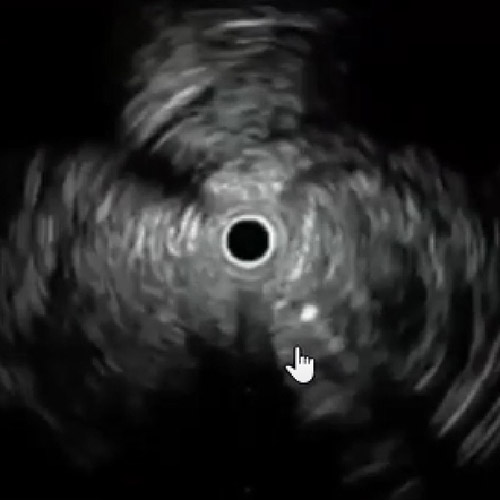

レトログレードから6gワイヤー(0,014“)で病変を通過させ、AnteOwl WRで確認したところ、石灰化部で偽腔を通過していることを確認した(図3)(図4)。

レトログレードからAnteOwl WRのTipDitection法でintra-plaque内を捉えた。今までのIVUS-GuideではAngio-Viewを都度振って対比していたが、最近は最初にAngioとIVUSのフュージョンを行い一方向に固定した上で、トランスデューサーの位置を変えながらワイヤーの距離やチップの向きを確認し、intra-plaque内を捉える手技に変化しつつある(図5)(図6)。